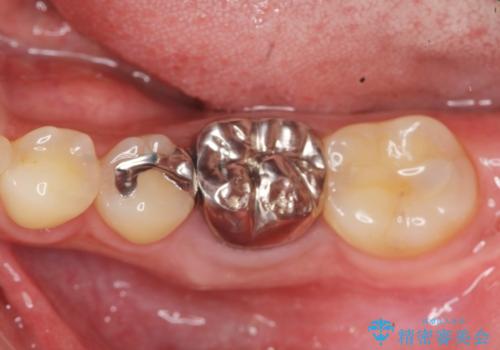

- 銀歯が揺れる、噛むと痛い、と治療を希望され来院されました。

銀歯・レジンコアを除去したところ、薄い残存歯質に亀裂が入り、保存が難しい状況が認められました。